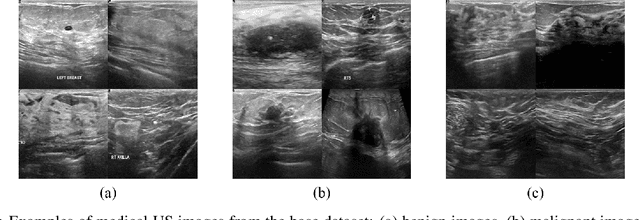

Abstract:Medical ultrasound (US) is one of the most widely used imaging modalities in clinical practice. However, its use presents unique challenges such as variable imaging quality. Deep learning (DL) can be used as an advanced medical US images analysis tool, while the performance of the DL model is greatly limited by the scarcity of big datasets. Here, we develop semi-supervised classification enhancement (SSCE) structures by constructing seven convolutional neural network (CNN) models and one of the most state-of-the-art generative adversarial network (GAN) models, StyleGAN2-ADA, to address this problem. A breast cancer dataset with 780 images is used as our base dataset. The results show that our SSCE structures obtain an accuracy of up to 97.9%, showing a maximum 21.6% improvement compared with utilizing CNN models alone and outperforming the previous methods using the same dataset by up to 23.9%. We believe our proposed state-of-the-art method can be regarded as a potential auxiliary tool for on-the-fly diagnoses of medical US images.